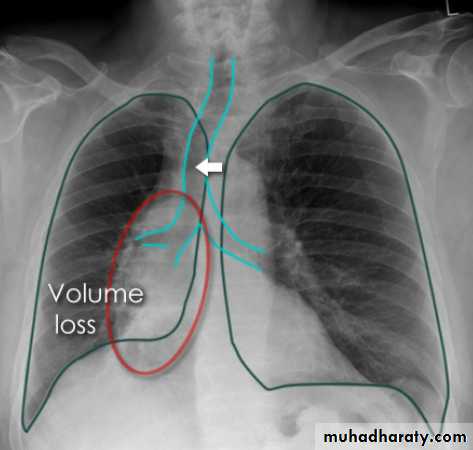

Right upper lobe collapse has distinctive features, and is usually easily identified on frontal chest radiographs .

Collapse of the right upper lobe is usually relatively easy to identify on frontal radiographs. Features consist of :

increased density in the upper medial aspect of the right hemithorax

elevation of the horizontal fissure

loss of the normal right medial cardiomediastinal contour

elevation of the right hilum

hyperinflation of the right middle and lower lobe result in increased translucency of the mid and lower parts of the right lung

right juxtaphrenic peak

A common cause of lobar collapse is a hilar mass. When a right hilar mass is combined with collapse of the right upper lobe, the result is an S shape to elevated horizontal fissure. This is known as Golden S sign .

Non-specific signs indicating right sided atelectasis are also usually present including:

elevation of the hemidiaphragm

crowding of the right sided ribs

shift of the mediastinum and trachea to the right